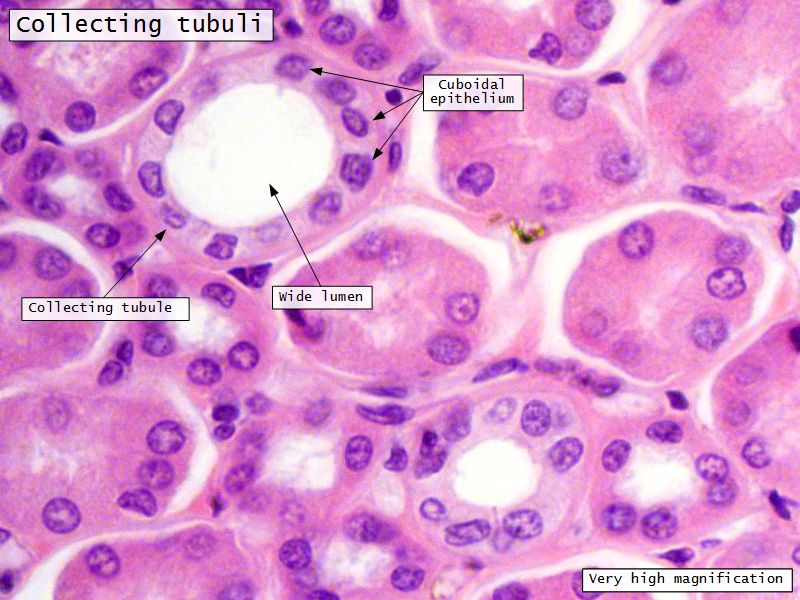

Collecting tubule

- Cuboidal to columnar epithelium

- Distinct lateral borders

Main collecting ducts

- Wide lumen

- Pale staining columnar cells